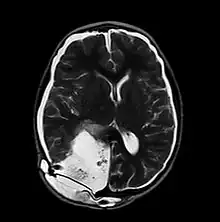

| MRI of Pseudomeningocele in 8 years old male patient | |

A pseudomeningocele is an abnormal collection of cerebrospinal fluid (CSF) that communicates with the CSF space around the brain or spinal cord. In contrast to a meningocele, in which the fluid is surrounded and confined by dura mater, in a pseudomeningocele, the fluid has no surrounding membrane, but is contained in a cavity within the soft tissues.